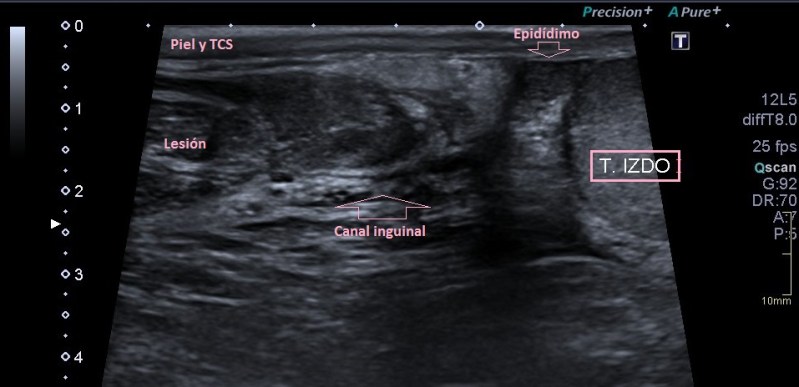

El paciente se presenta con una lesión tipo bulto en la región inguinal con una sospecha de su médico de familia de hernia inguinal. Al realizar este estudio, enseguida, el técnico que realiza la exploración se da cuenta que el patrón de comportamiento de la lesión no es la de una lesión herniaria aunque su aspecto pudiera parecerlo en un primer momento. Procede con el protocolo habitual de estudio para bultomas, localización, estudio, medida y vascularización, además, de maniobra de valsalva para descartar una hernia.

Así en esta imagen podemos ver que tienen criterio ultrasonográfico de hernia inguinal, más raro, pero posible, de lipoma, el problema para la primera opción es que con la maniobra de valsalva la lesión era inmóvil. Cuando estudias una lesión no solo es importante la semiología, también su comportamiento y la relación que tiene con los tejidos adyacentes.

La anatomía ecográfica no deja lugar a dudas de la localización llegando muy cerca del testículo, ocupando el canal inguinal.

La lesión era bastante grande , ocupaba como ves en la imagen una parte importe del canal inguinal también en la imagen 7.

Se completa estudio con Ct ante las características de la lesión y la imagen que tenemos, muy llamativa, refrenda la presencia de una lesión en el canal inguinal que posee una gran calcificación.  En el CT se objetiva, imagen 7, una afectación ligeramente mayor a la estimada en el estudio ecográfico. La sospecha para la radióloga fue de lesión primaria de cordón inguinal compatible con Liposarcoma, a tenor de todos lo hallazgos en las dos pruebas, basándose principalmente en la heterogenicidad de la imagen, la calcificación y el comportamiento no compatible con hernia inguinal ni con la semiología típica del lipoma.